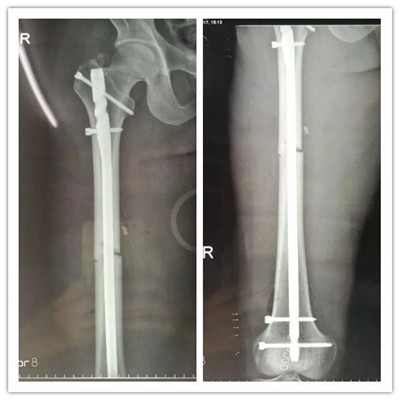

經(jīng)過慎重考慮和周密的術(shù)前計劃,羅軍主任帶領(lǐng)帶領(lǐng)科室團隊用骨折閉合復(fù)位髓內(nèi)釘固定的微創(chuàng)方法為患者進行手術(shù)。 近90分鐘的精心手術(shù),骨折處沒有切開,采用間接復(fù)位的方法就使骨折塊達(dá)到了解剖復(fù)位,并用微創(chuàng)切口導(dǎo)入髓內(nèi)釘對骨折進行了牢固的固定,圍手術(shù)期沒有輸血,醫(yī)療費用也明顯降低。

▲骨折的完美復(fù)位和內(nèi)固定

由于傷口小,出血少,術(shù)后疼痛很快減輕,患者術(shù)后僅一天就可以開始扶拐下地活動并進行康復(fù)鍛煉。